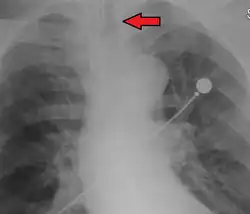

Ideally, at least one of the methods utilized for confirming tracheal tube placement will be a measuring instrument. Waveform capnography has emerged as the gold standard for the confirmation of tube placement within the trachea. Other methods relying on instruments include the use of a colorimetric end-tidal carbon dioxide detector, a self-inflating esophageal bulb, or an esophageal detection device.[35] The distal tip of a properly positioned tracheal tube will be located in the mid-trachea, roughly 2 cm (1 in) above the bifurcation of the carina; this can be confirmed by chest x-ray. If it is inserted too far into the trachea (beyond the carina), the tip of the tracheal tube is likely to be within the right main bronchus—a situation often referred to as a "right mainstem intubation". In this situation, the left lung may be unable to participate in ventilation, which can lead to decreased oxygen content due to ventilation/perfusion mismatch.[36]